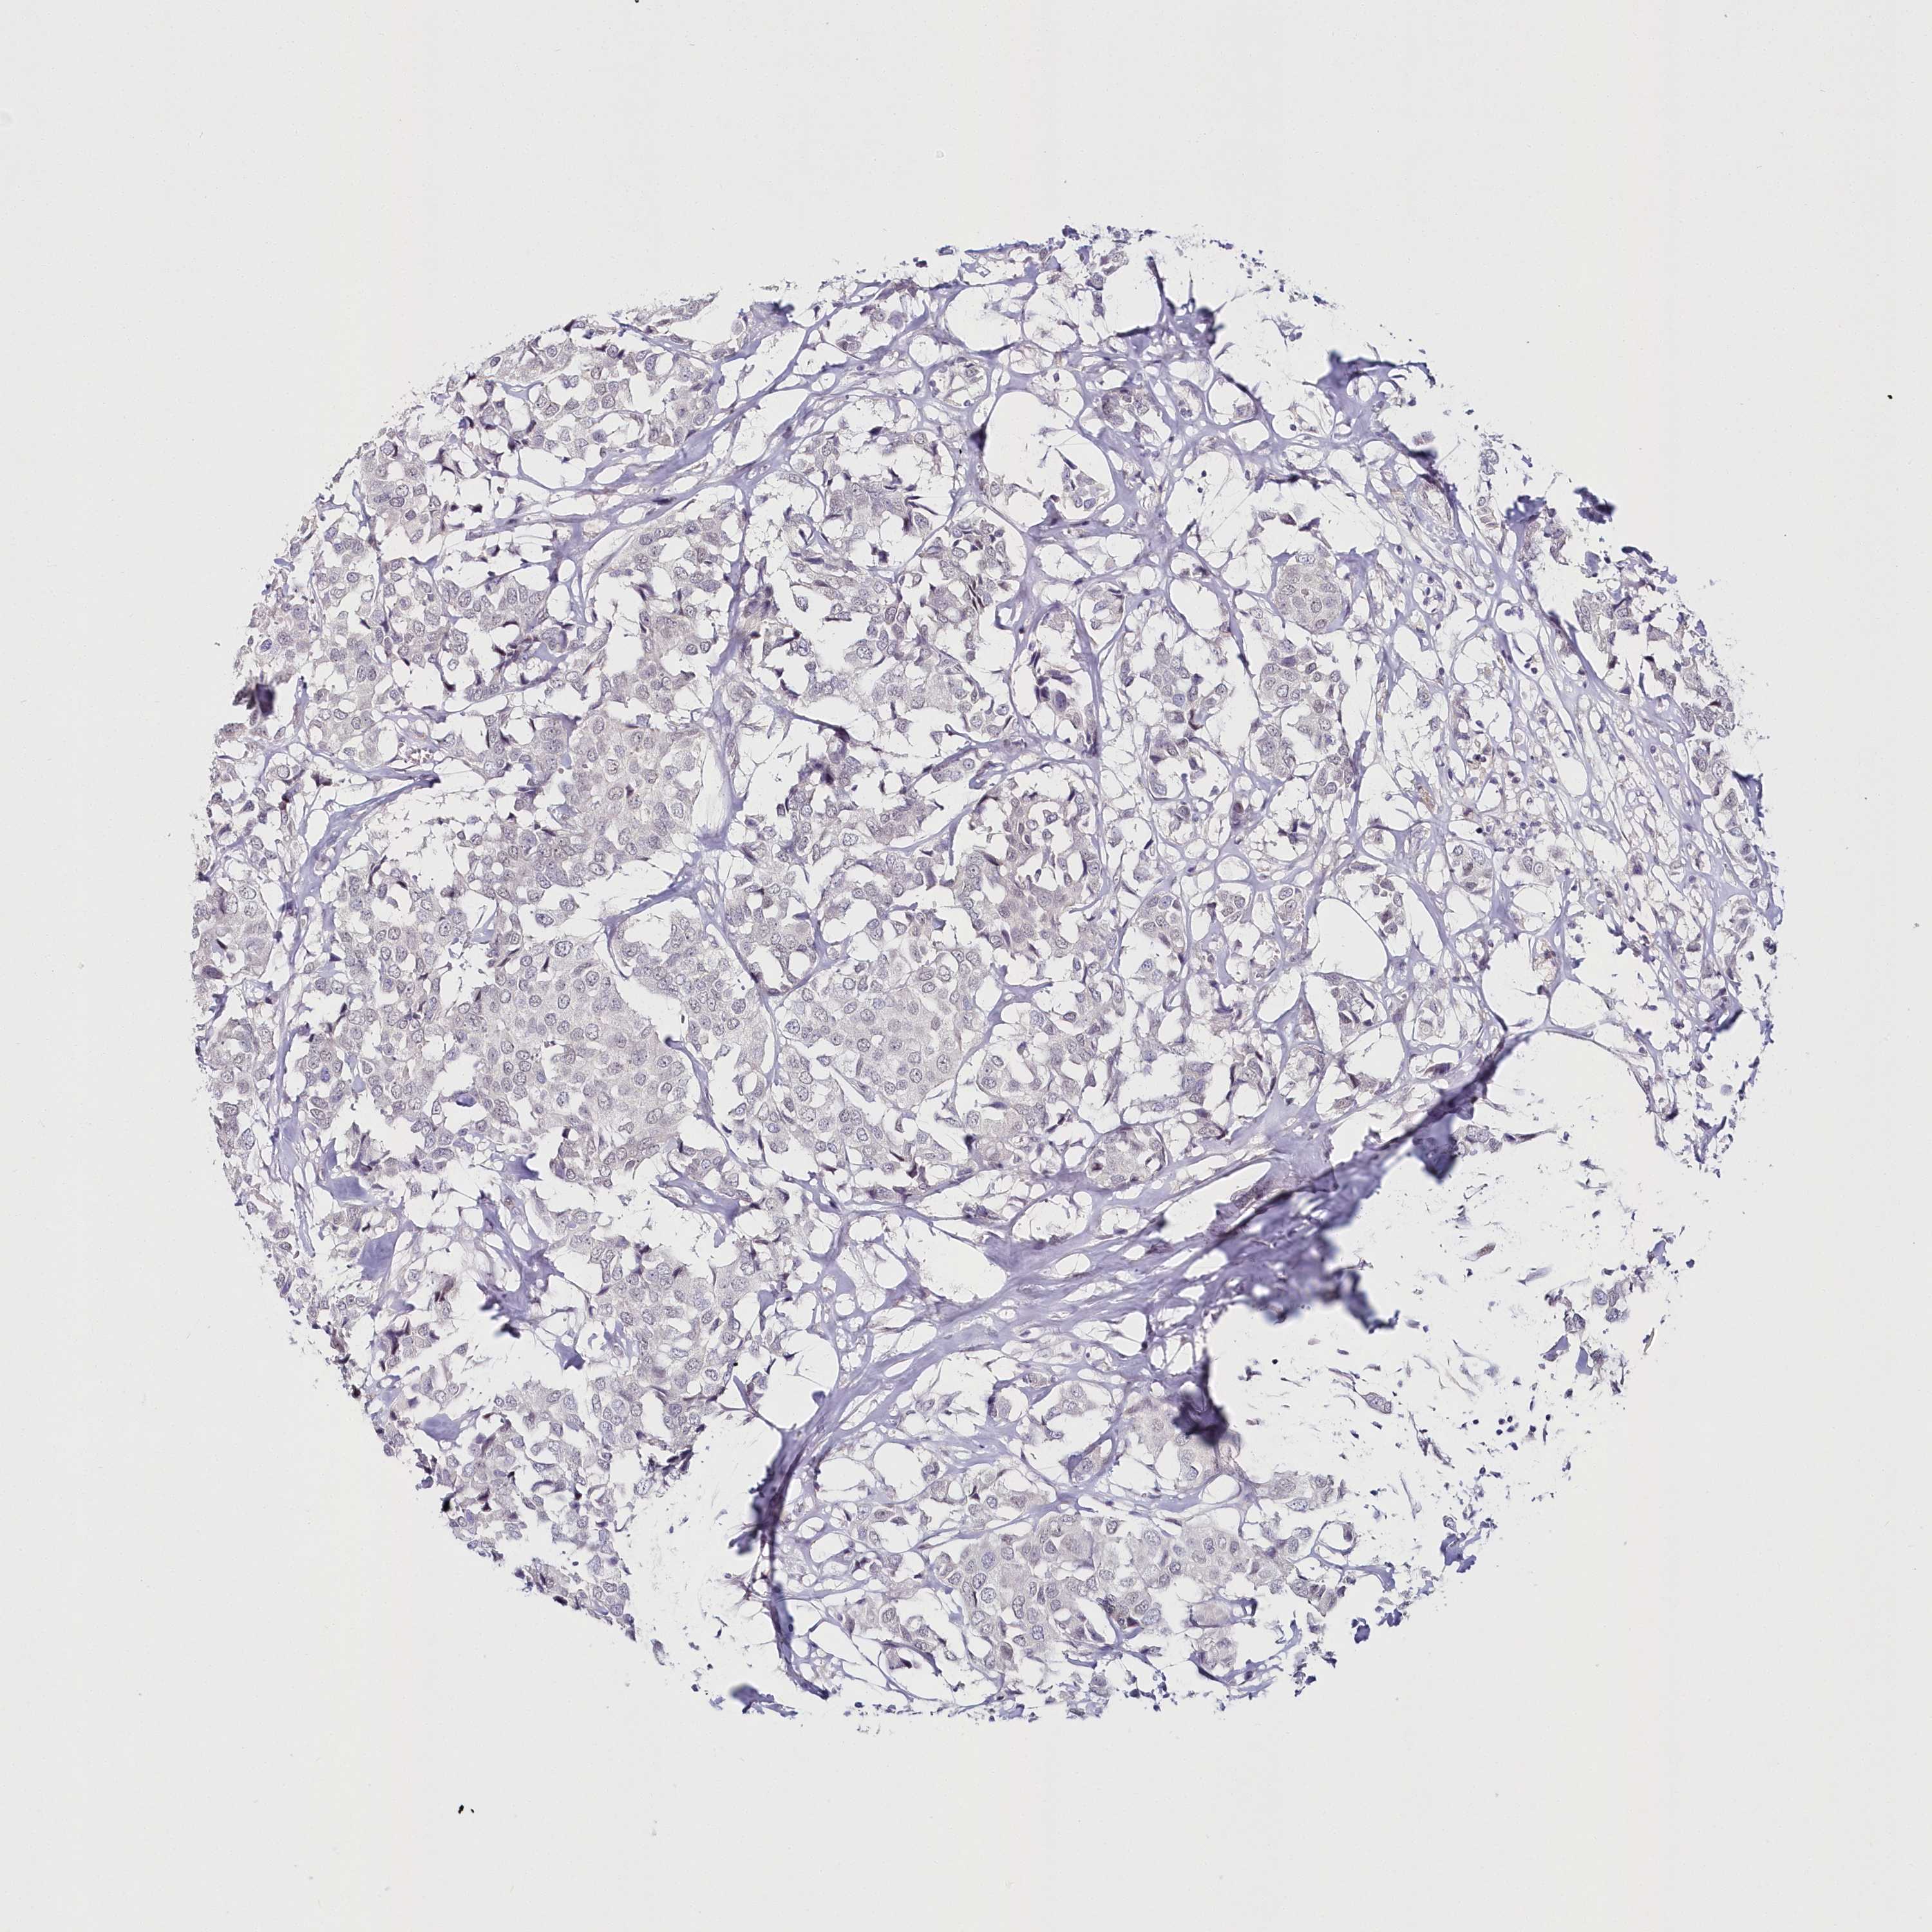

CANCER BREAST CANCER Show tissue menu

BRCA TCGA BRCA VALIDATION PROTEIN EXPRESSION